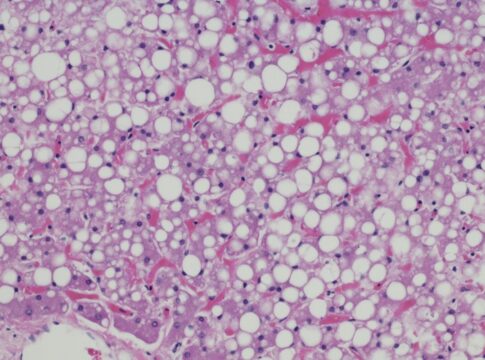

Uma condição cada vez mais comum, a esteatose hepática, conhecida como gordura no fígado, é uma doença de estilo de vida. Desencadeado por obesidade, má alimentação, sedentarismo e excesso de álcool, o acúmulo excessivo de gordura nas células hepáticas é preocupante e pode causar problemas sérios de saúde, como cirrose e até câncer.

O gastroenterologista e hepatologista Rodrigo Rêgo Barros conta que o diagnóstico precoce é fundamental. “A esteatose hepática é uma condição reversível quando diagnosticada precocemente. Com uma alimentação equilibrada, prática regular de exercícios e controle do peso corporal, o fígado tende a se regenerar e eliminar o excesso de gordura”, afirma o médico.